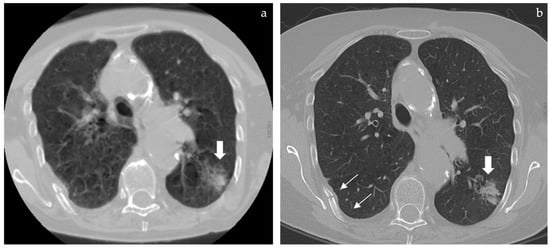

Figure 2. (a) (left) and (b) (right): whenever a lung opacity is spotted by chance in spine CT a full FOV reconstruction can be performed but only if RAW data are still available in the scanner. In the case (previously described in Figure 1) this allowed us to rule out further opacities but the respiratory motion artifacts prevented a proper characterization of the main lung finding that appeared as a blurry edged opacity (a, large arrow). The patient was called back and a standard thoracic CT was repeated to better define the lung finding that appeared as a subsolid ground glass opacity compatible with a lepidic growth adenocarcinoma (b, large arrow) as later confirmed by lung biopsy. In both full FOV reconstructions a rib fracture was detected (b, thin arrows).